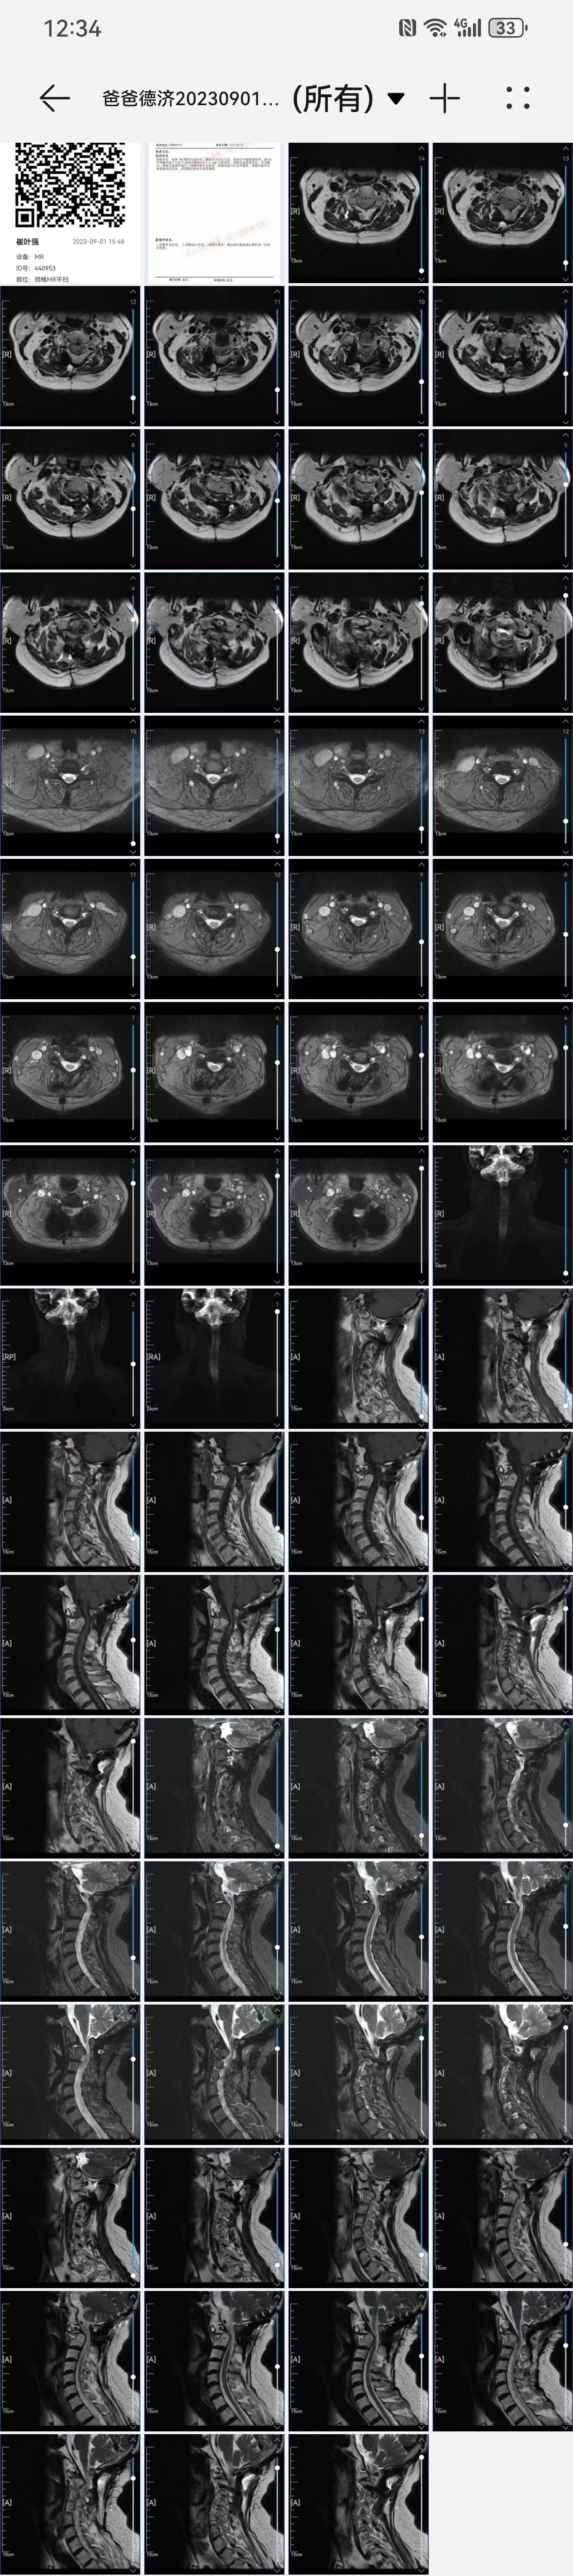

• 2023.09.01,复查,压迫脊髓。

• 术后影像: